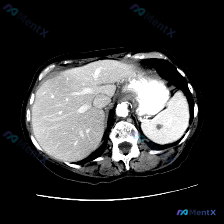

最近看到一份腹部平扫CT的影像资料,主要异常集中在脾脏,整理了一下读片和分析思路,和大家分享。 先整理一下核心影像事实 这是一张腹部CT软组织窗横断面图像,主要发现如下: 1. 肝脏:实质密度尚均匀,未见明确局灶性占位,肝叶比例、血管走行基本正常 2. 脾脏:形态正常,但脾实质内可见一个圆形、边界相...